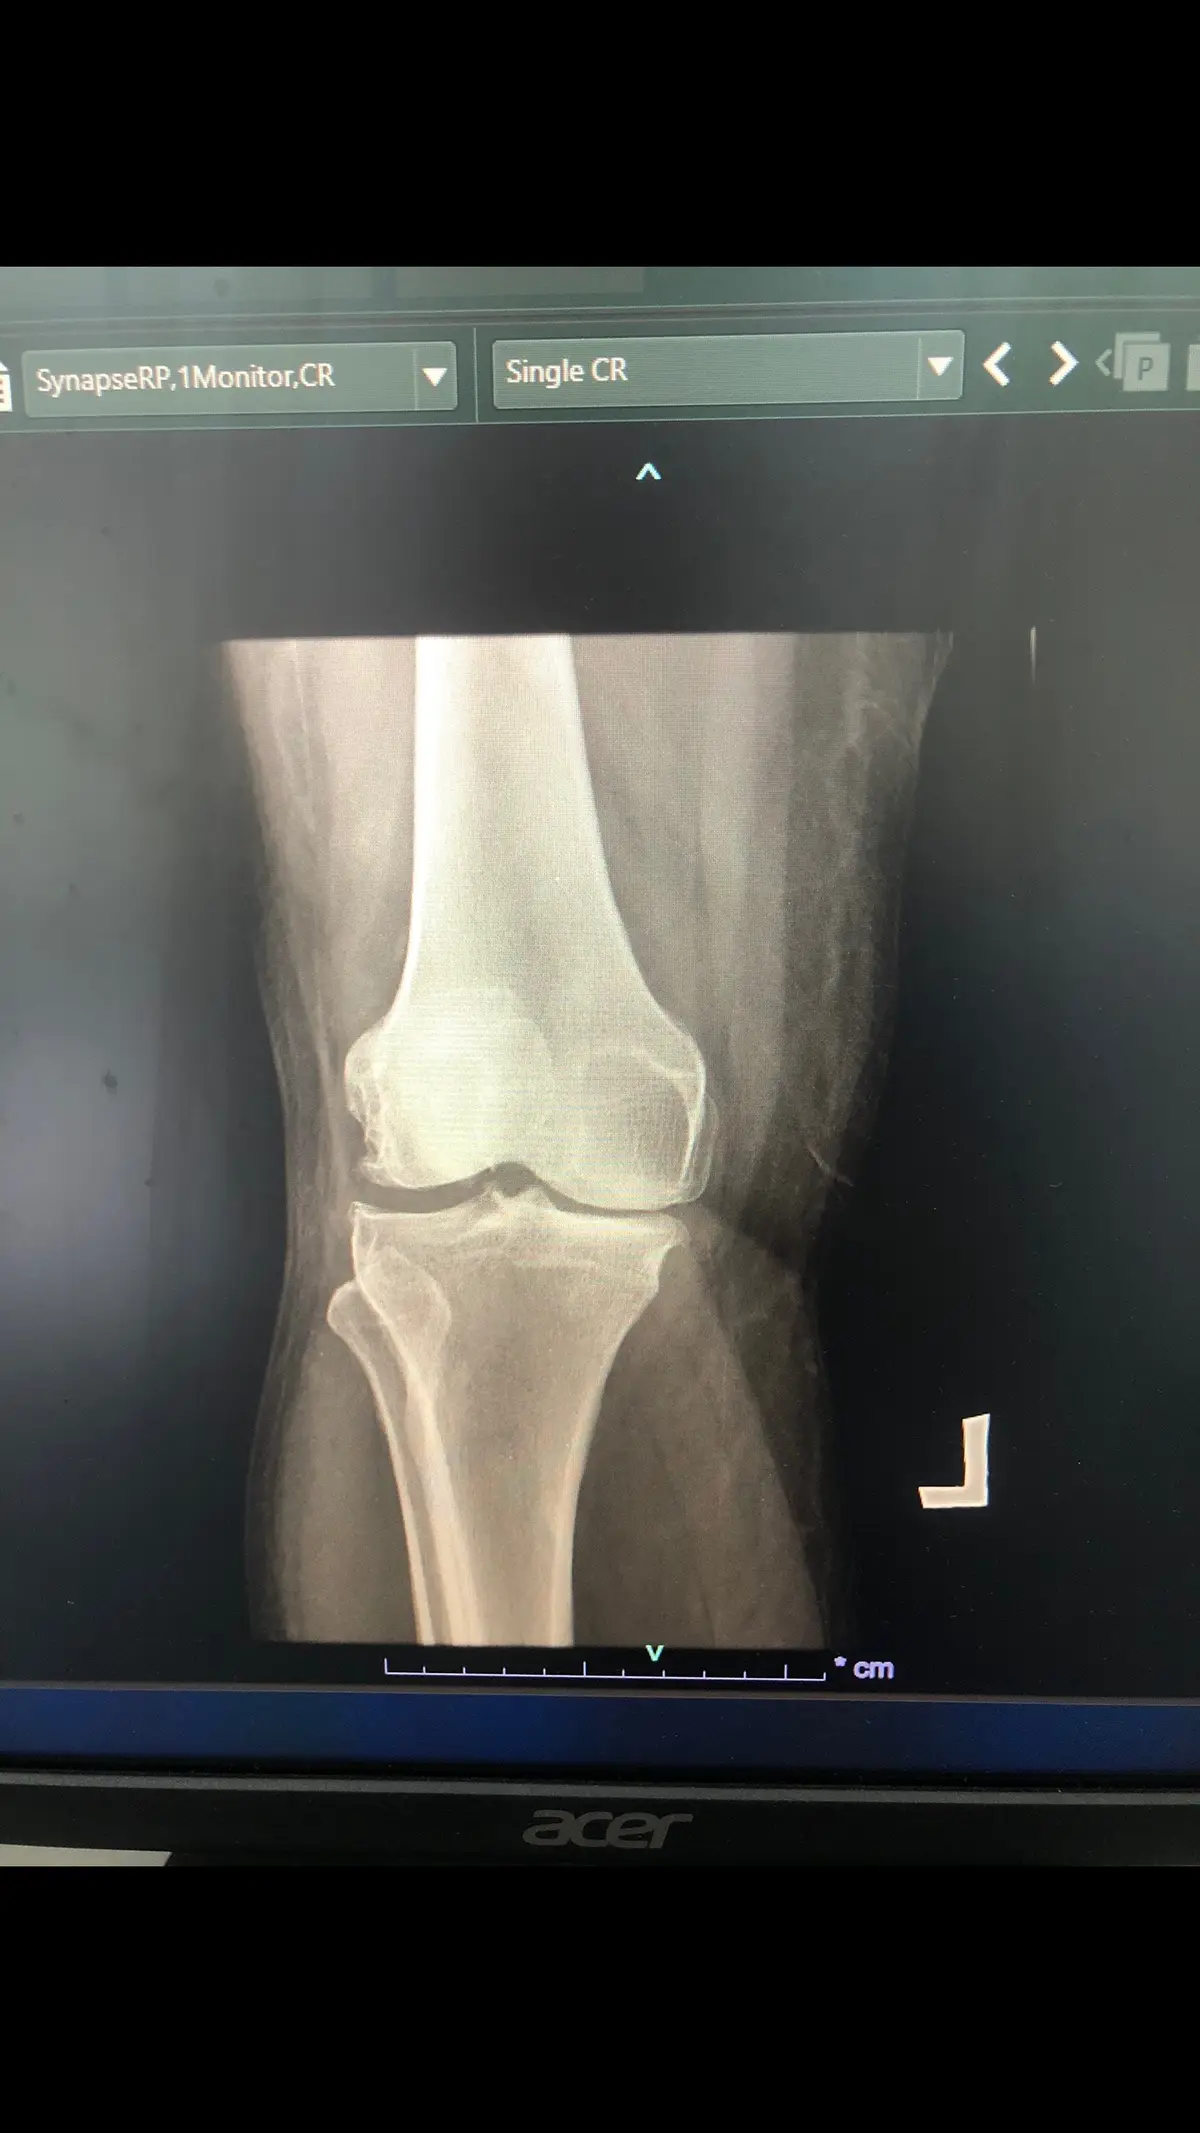

Gambar x ray pesakit yang ada osteoarthritis (radang sendi) lutut kanan. Rawatan fisio: 1.ice/hotpack untuk mengurangkan sakit dan bengkak 2.senaman regangan dan kuatkan otot,maintainkan pergerakkan sendi lutut 3.gait training 4.patient education #physiotherapy #osteorartritis